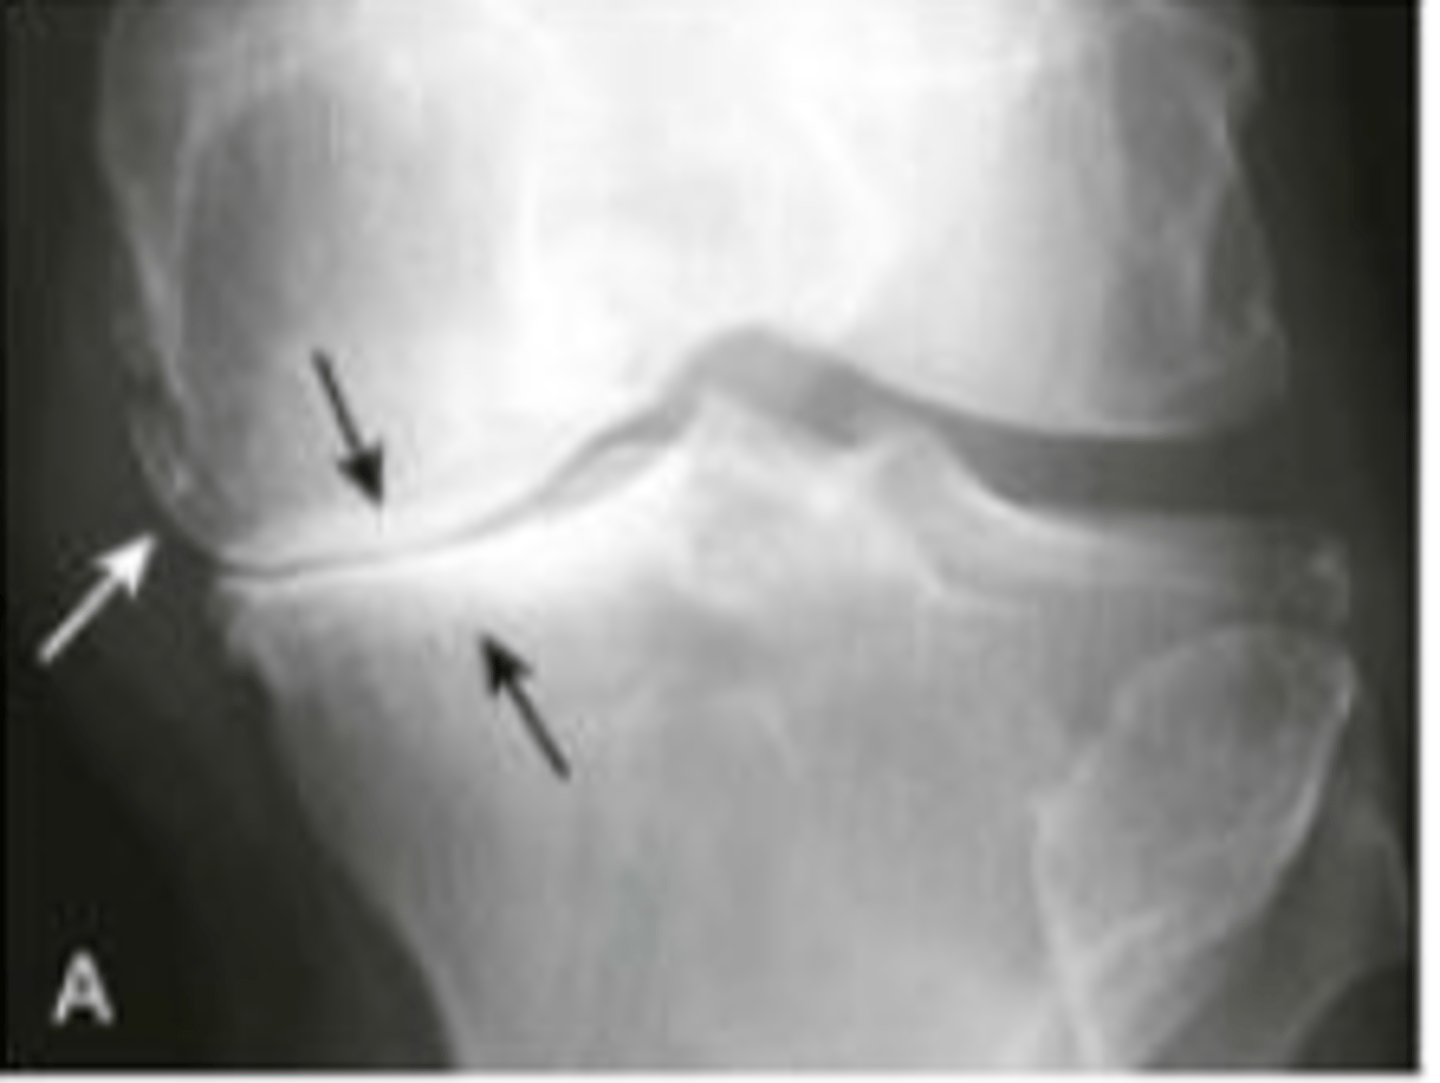

osteoarthritis

subchondral sclerosis, joint narrowing, osteophytes

secondary osteoarthritis

joint space barely visible , subchondral sclerosis, phleboliths, cysts

hypertrophic arthritis

bone formation at the site of involved joint

- osteophyte formations

- subchondral sclerosis

- subchondral cysts

- narrowing of joint space